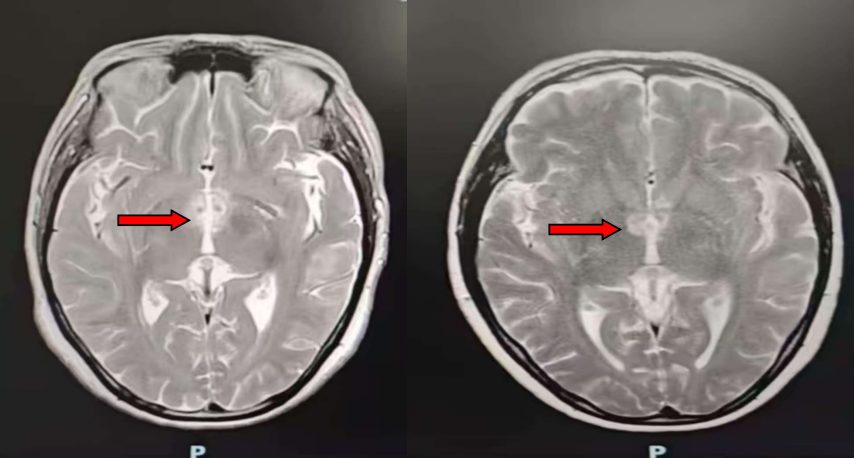

风湿免疫科欧阳楚君副主任接诊后,发现患者自身抗体谱更符合干燥综合征,需鉴别颅内感染与原发病活动,随即安排头颅MRA、腰椎穿刺及脑脊液相关检测。鉴于病情复杂,科室迅速启动多学科协作诊疗(MDT),联合神经内科、呼吸科等多科室专家会诊。结合影像学双侧丘脑及颈髓异常信号、脑脊液AQP4抗体阳性结果,最终明确诊断为“干燥综合征合并视神经脊髓炎”。

△治疗前头颅MR提示双侧丘脑内侧、灰结节脑实质异常信号影

治疗后双侧丘脑内侧、灰结节脑实质异常信号影减轻